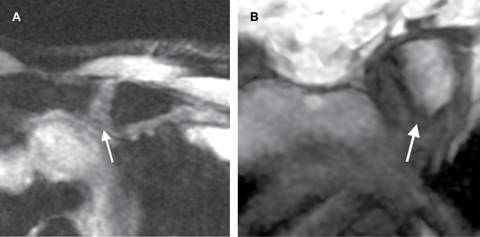

Los hallazgos característicos por resonancia magnética son engrosamiento del cartílago con aumento en la intensidad de señal de manera focal o generalizada en secuencias T2, STIR o T2 Fat Sat, edema subcondral y reforzamiento tras la administración de medio de contraste (Figura 2).

Figura 2: Resonancia magnética; A) plano axial con edema del cartílago articular en secuencia STIR; B) plano coronal secuencia T1 erosiones subcondrales de predominio en la región interna de la articulación esternoclavicular izquierda.